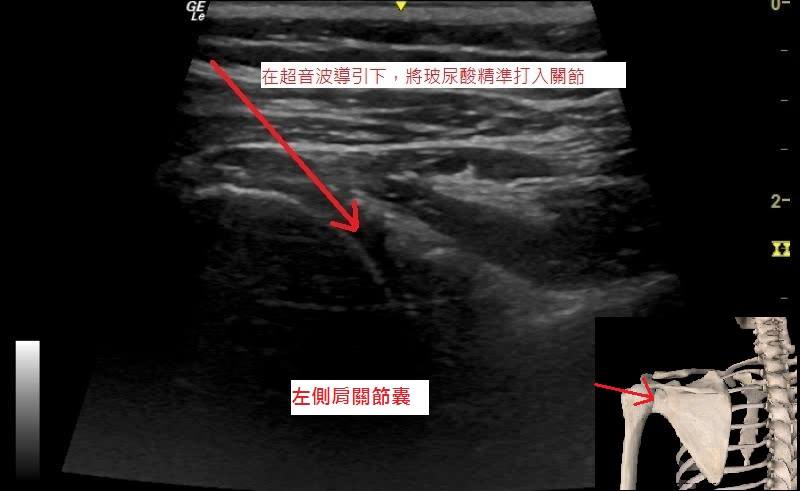

超音波可輔助醫師作精準注射。

【圖1&2】肩痛的患者,超音波可以協助診斷肩關節問題及輔助醫師精準注射。